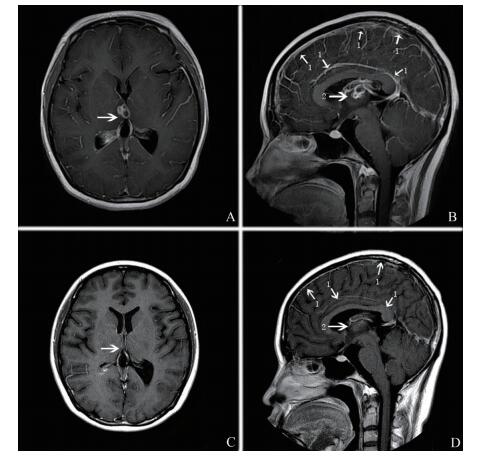

例3 患者男,26岁。因“头痛伴发热10 d”于2017年10月24日入中山大学附属第三医院。入院前10 d患者开始出现持续性头痛,不能缓解,后逐渐出现发热,伴有寒战,视物模糊,无恶心、呕吐、肢体运动障碍、大小便失禁、神志不清。有SLE病史3月余。发病前规律口服泼尼松50 mg、1次/日,2017年8月4日及8月8日在外院行环磷酰胺冲击治疗及地塞米松+甲氨蝶呤鞘内注射。入院时体格检查:体温36℃,神志清晰,对答切题,双侧瞳孔等圆等大,直径3 mm,对光反射灵敏,眼球各方位活动正常,双侧眼底未见视乳头水肿。四肢肌张力正常,四肢肌力5级,双侧巴宾斯基征阴性。颈软,颌胸距2 cm,克匿征阴性,布鲁津斯基征阴性。心、肺、腹未见异常。实验室及辅助检查:血白细胞9.25×109/L,中性粒细胞0.86。腰椎穿刺示脑脊液压力80 mm H2O,白细胞1 521×106/L,糖0.26 mmol/L,氯107.7 mmol/L,蛋白3.07 g/L。脑脊液涂片未发现病原体,脑脊液病原体培养阴性。头颅MRI示脑膜脑炎并双侧额叶,左侧侧脑室后角多发脓肿形成,周围水肿,脑室炎、左侧脉络丛炎(图 3A、B)。脑脊液mNGS示诺卡菌、序列数12、置信度中。诊断为诺卡菌脑膜脑炎,予磺胺甲

图 3 CNS诺卡菌感染例3患者头颅MRI 治疗前颅脑MRI增强图像,左侧侧脑室后角旁见一类圆形病灶,增强扫描环状强化,病灶周围水肿明显(A、B箭头所指处) |

诺卡菌感染与其它脑脓肿一样,MRI下注射钆后显示出病变的坏死中心和多叶厚壁环状强化,T2加权像上的周边环形低信号被认为是由坏死组织碎片和巨噬细胞对夹膜的吞噬作用所形成,而厚荚膜的产生是因为诺卡菌生长缓慢及宿主抵抗细菌的过程中所发生的外周变化[9-10]。诺卡菌感染若能早期治疗,病灶可明显减少、缩小。